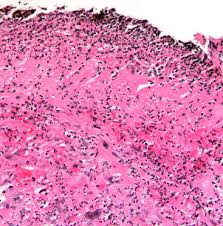

For hsv, the viral cytopathic features are usually present adjacent to the ulcer, because the virus infects the squamous epithelial cells. Virtual international pathology institute (vipi). Herpes esophagitis is one of the infectious esophagitis that usually affects immunocompromised patients. Fortschritt in der medizin, heidelberg. Welcome to the atlas of pathology website. Epidemiology it occurs as an opportunistic infection in immunocompromised patients, particularly those with aids. A cmv immunostain confirmed a diagnosis of cmv esophagitis. Report of 3 cases and review of the literature. The disease is increasingly recognized in recent decades. Within you will find microscopic explained images of basic pathology lesions along with accompanying text. Canalejo castrillero e, garcía durán f, cabello n, garcía martínez j. Herpes esophagitis is a viral infection of the esophagus caused by herpes simplex virus (hsv). We here present a case of hsv esophagitis that was presented with its characteristic features.

A cmv immunostain confirmed a diagnosis of cmv esophagitis. Causes of esophagitis include stomach acids backing up into the esophagus, infection, oral medications and allergies. For hsv, the viral cytopathic features are usually present adjacent to the ulcer, because the virus infects the squamous epithelial cells. Although hsv esophagitis is much more common in immunosuppressed individuals, it can occur in healthy persons. May cause esophageal perforation or disseminate in immunocompromised patients. Associated with cmv or hsv esophagitis in immunocompromised (see case reports below); Candida esophagitis (see the image below) is the most common type of infectious esophagitis. The majority of patients with eosinophilic esophagitis have a personal history of allergic disorders such as bronchial asthma, allergic rhinitis, allergic.